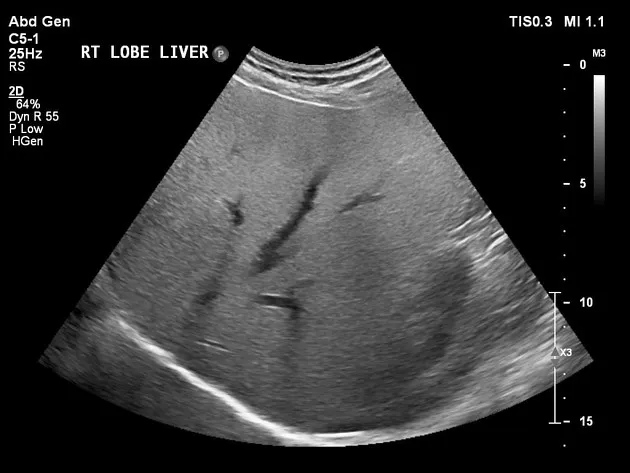

Doador vivo: quais critérios clínicos importam no aconselhamento pré-doação em mulheres com desejo de gestar?

Doação renal em mulheres jovens pode impactar mais o feto do que a mãe — e esse dado muda o pré-operatório. O maior estudo já feito mostra aumento de PIG e sinais de disfunção placentária silenciosa, especialmente em nulíparas. Se você ainda não discute isso de forma explícita no consentimento, talvez esteja subestimando o risco.